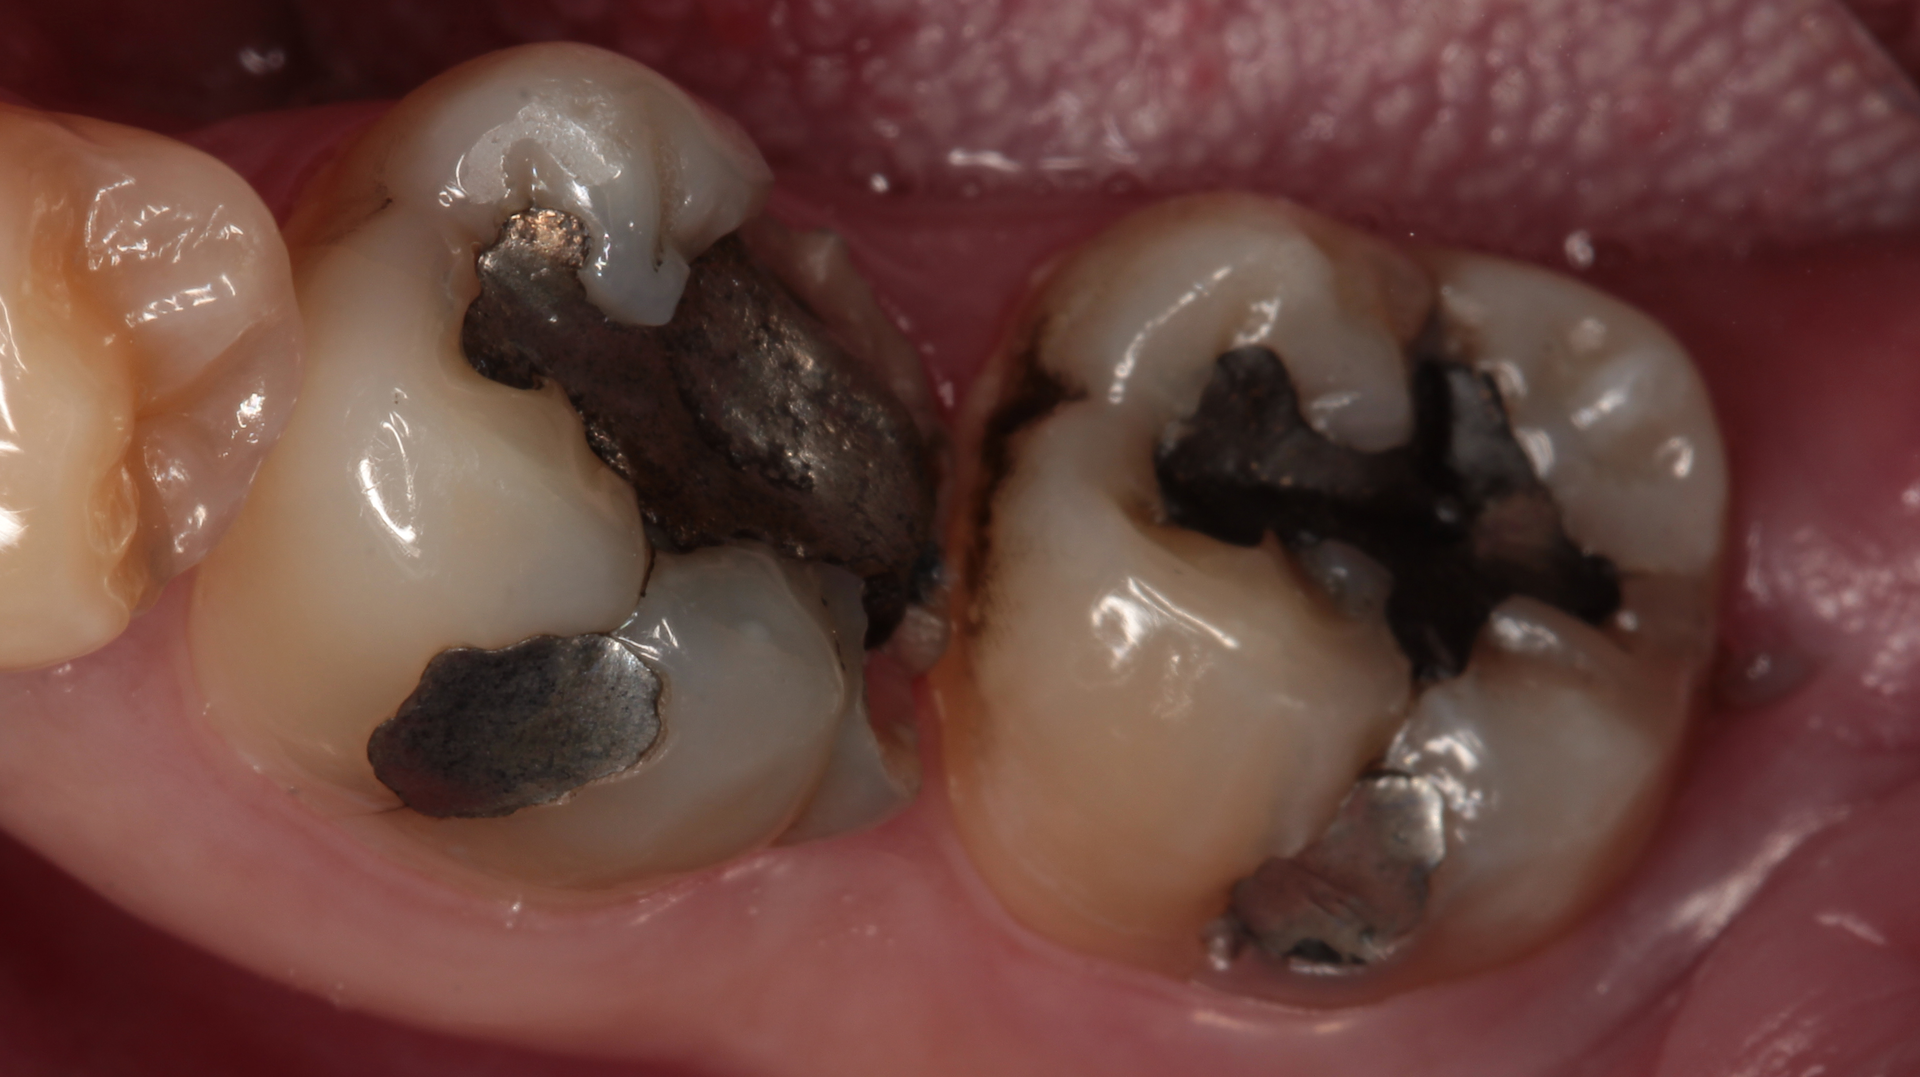

A patient presents with large cavities that have been previously addressed with amalgam. After removing the amalgam and achieving isolation, an alginate is used to take an impression (figures 1–4). A working model is made by first placing light silicone material in the impression and then supporting it with putty to provide rigidity (figures 5a-c). A second working model is made to allow for “flexion” of the dies. This allows separation of the individual teeth and preparations for adjusting proximal margins and interproximal contacts of the restoration as needed.

In this case we take advantage of the rubberized resin properties of Activa Presto (Pulpdent Corporation), a universal light-cure composite, to ensure that the occlusal impacts are dispersed in the best way and thus transmit the least amount of stress to the tooth (figures 6a-c–9). In addition, the biomimicking properties of Activa Presto give us the assurance that the restored area will be continuously adjusted to the margins. The restorations are cemented with Activa BioActive-Cement (Pulpdent Corporation) to ensure that the properties of the composite resin are shared by the cement (figure 10).